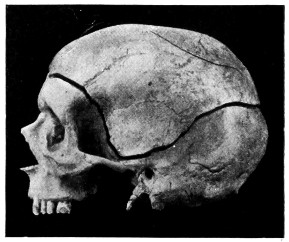

| 42. A comminuted fracture of the skull | 112 |

| 43 A and B. An explosive fracture of the vault of the skull | 113 |

| 44. A temperature chart illustrating the changes in temperature observed in head-injuries | 117 |